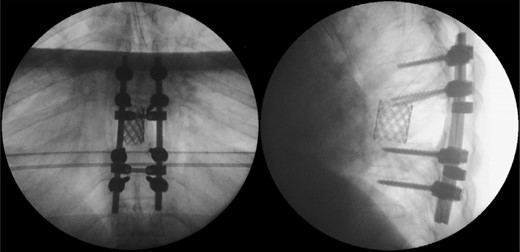

Due to the advanced stage of the lesion, with associated instability that could result in major neurologic deficits in a short time period, a total en bloc spondylectomy of T8 by a posterior-only approach was performed (Fig. 2). The operation followed the technique proposed by Tomita et al. and was complemented with anterior-column reconstruction with a titanium mesh filled with structural allograft, as well as pedicle screw instrumentation, from T6 to T10 (Fig. 3). During the procedure, the eighth dorsal nerve routes were sacrificed.

Intraoperative photographs; after total en bloc spondylectomy (A), anterior-column reconstruction was accomplished with placement of a titanium cage with structural allograft (B) and was complemented with pedicle screw-rod fixation (C). (D) Resected vertebra.